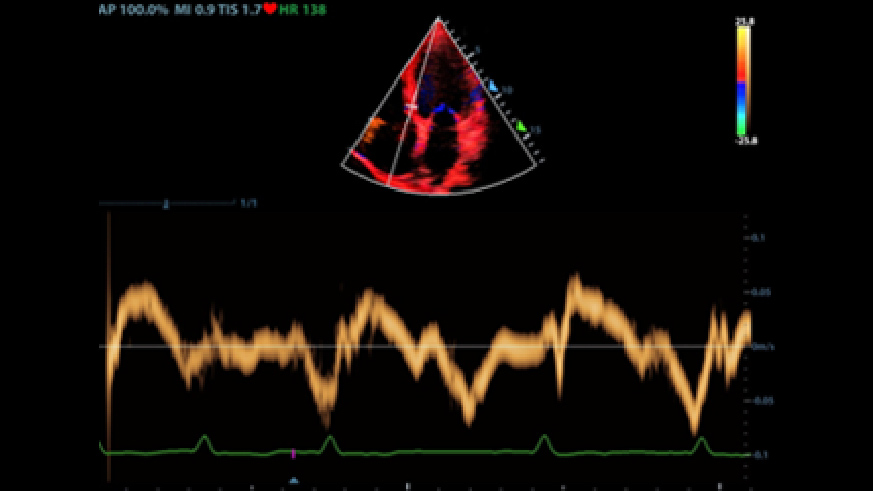

2Smart VTI

Automatic measurement of the VTI (Velocity Time Integral) and CO (Cardiac Output), for rapid assessment of cardiac function. Automatically locate color box and PW sample line on real time. A graph of parameters trends about CO, SV and VTI to guide the decision-making.

3Smart IVC

Automatic measurement of IVC (Inferior Vena Cava) parameters, helps for volume status assessment and guides the fluid therapy. A graph of parameters change about CI or DI and IVCV for monitoring the change of critical ill patients.